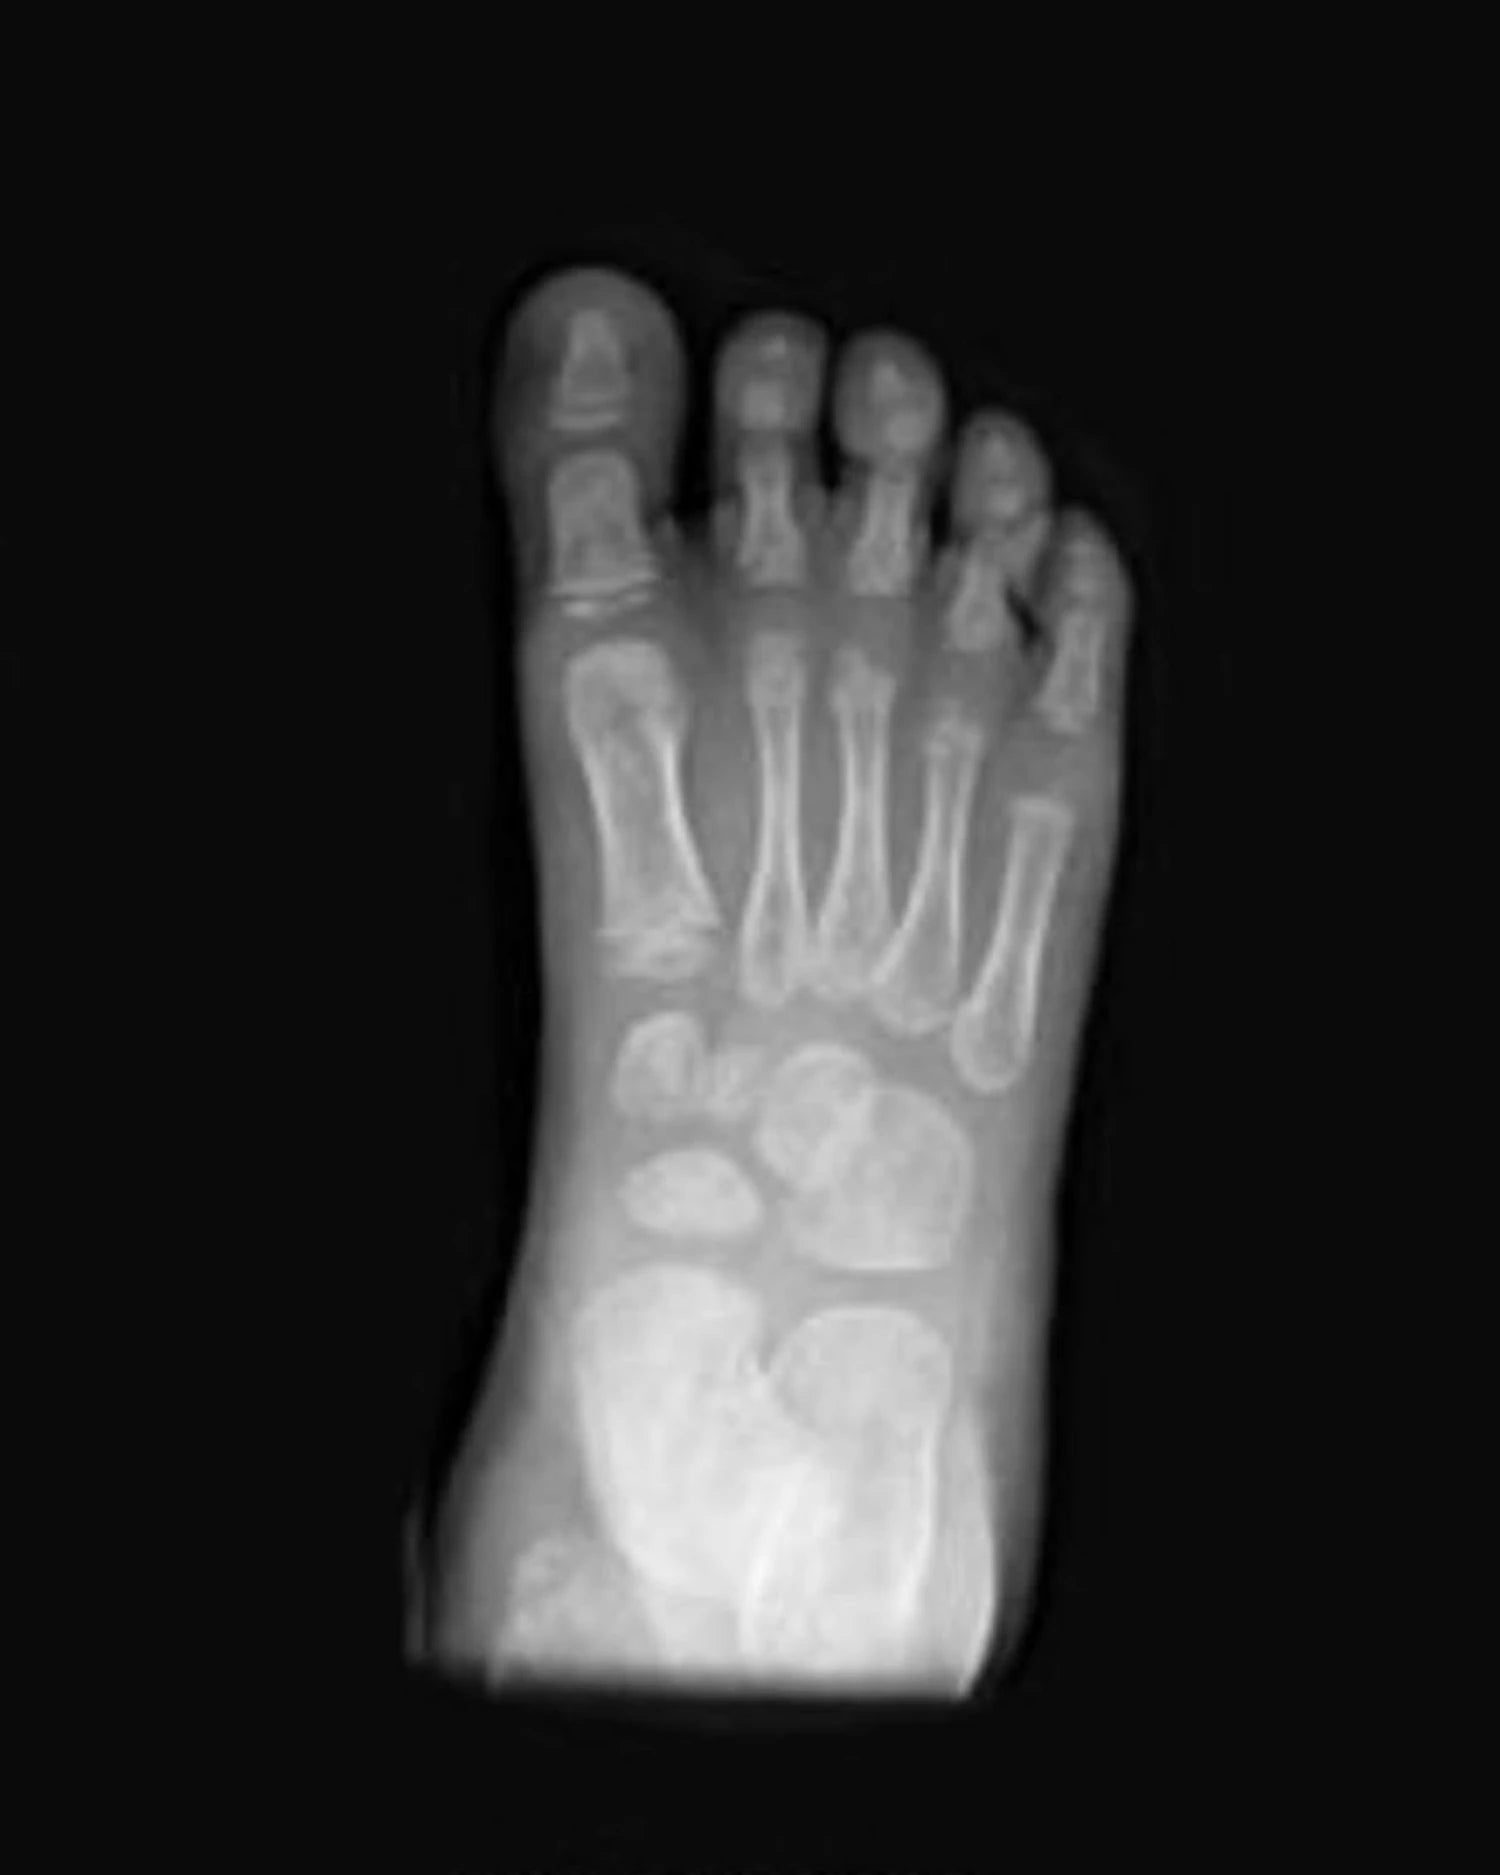

Puntera ancha: pie libre frente a pie comprimido

La horma Gullibare está diseñada para imitar la forma natural del pie de un bebé. Es más ancha en la parte de los dedos para que puedan abrirse y moverse con libertad.

Esto es esencial para un desarrollo saludable del equilibrio, la estabilidad y una distribución uniforme del peso.